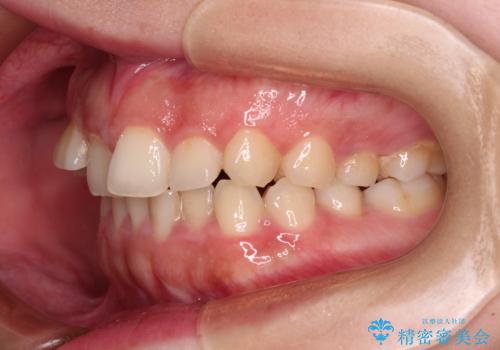

捻れて前に出ている前歯 ワイヤー装置での非抜歯矯正

- 捻れて前に出ている上顎前歯と全体的なデコボコを気にして来院された患者様です。

口元の突出感は強くなかったため非抜歯矯正での対応となりますが、捻転を改善する際に上顎前歯が前突する可能性があったため、上顎臼歯部にアンカースクリューを使用して、歯列が前方に転位しないようにすることとしました。